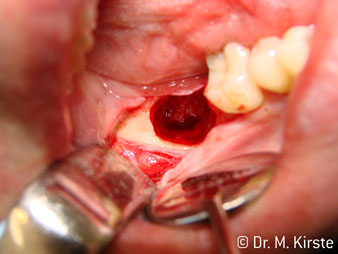

The 45° angle of the handpiece has been specially selected for its wide range of advantages. Colleagues who work in surgery, and for whom this handpiece was primarily developed, will soon appreciate the ability to work efficiently in very restricted spaces. In wisdom tooth extractions in particular (fig. 2) there is no need for large-scale spreading of the soft tissues in the cheek region (fig. 3). The design of the handpiece head combined with turning the head slightly during preparation allows work to be carried out quickly and safely in the retromolar region.

The professional design of the bearings inside the handpiece head guarantees quiet running of the bur; this makes for an impressively atraumatic cut in the separation of tooth and root (fig. 4-9).

Fig. 3

Fig. 5